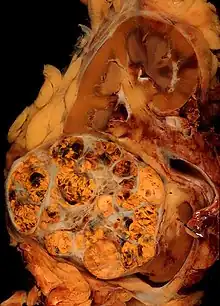

Histopathology

The gross and microscopic appearance of renal cell carcinomas is highly variable. The renal cell carcinoma may present reddened areas where blood vessels have bled, and cysts containing watery fluids.[58] The body of the tumour shows large blood vessels that have walls composed of cancerous cells. Gross examination often shows a yellowish, multilobulated tumor in the renal cortex, which frequently contains zones of necrosis, haemorrhage and scarring. In a microscopic context, there are four major histologic subtypes of renal cell cancer: clear cell (conventional RCC, 75%), papillary (15%), chromophobic (5%), and collecting duct (2%). Sarcomatoid changes (morphology and patterns of IHC that mimic sarcoma, spindle cells) can be observed within any RCC subtype and are associated with more aggressive clinical course and worse prognosis. Under light microscopy, these tumour cells can exhibit papillae, tubules or nests, and are quite large, atypical, and polygonal.

Recent studies have brought attention to the close association of the type of cancerous cells to the aggressiveness of the condition. Some studies suggest that these cancerous cells accumulate glycogen and lipids, their cytoplasm appear "clear", the nuclei remain in the middle of the cells, and the cellular membrane is evident.[59] Some cells may be smaller, with eosinophilic cytoplasm, resembling normal tubular cells. The stroma is reduced, but well vascularised. The tumour compresses the surrounding parenchyma, producing a pseudocapsule.[60]

The most common cell type exhibited by renal cell carcinoma is the clear cell, which is named by the dissolving of the cells' high lipid content in the cytoplasm. The clear cells are thought to be the least likely to spread and usually respond more favourably to treatment. However, most of the tumours contain a mixture of cells. The most aggressive stage of renal cancer is believed to be the one in which the tumour is mixed, containing both clear and granular cells.[61]